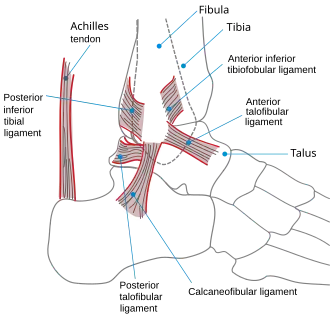

Ligaments

The ankle joint is bound by the strong deltoid ligament and three lateral ligaments: the anterior talofibular ligament, the posterior talofibular ligament, and the calcaneofibular ligament.

- The deltoid ligament supports the medial side of the joint, and is attached at the medial malleolus of the tibia and connect in four places to the talar shelf of the calcaneus, calcaneonavicular ligament, the navicular tuberosity, and to the medial surface of the talus.

- The anterior and posterior talofibular ligaments support the lateral side of the joint from the lateral malleolus of the fibula to the dorsal and ventral ends of the talus.

- The calcaneofibular ligament is attached at the lateral malleolus and to the lateral surface of the calcaneus.

Though it does not span the ankle joint itself, the syndesmotic ligament makes an important contribution to the stability of the ankle. This ligament spans the syndesmosis, i.e. the articulation between the medial aspect of the distal fibula and the lateral aspect of the distal tibia. An isolated injury to this ligament is often called a high ankle sprain.

The bony architecture of the ankle joint is most stable in dorsiflexion.[14] Thus, a sprained ankle is more likely to occur when the ankle is plantar-flexed,[15] as ligamentous support is more important in this position. The classic ankle sprain involves the anterior talofibular ligament (ATFL), which is also the most commonly injured ligament during inversion sprains. Another ligament that can be injured in a severe ankle sprain is the calcaneofibular ligament.